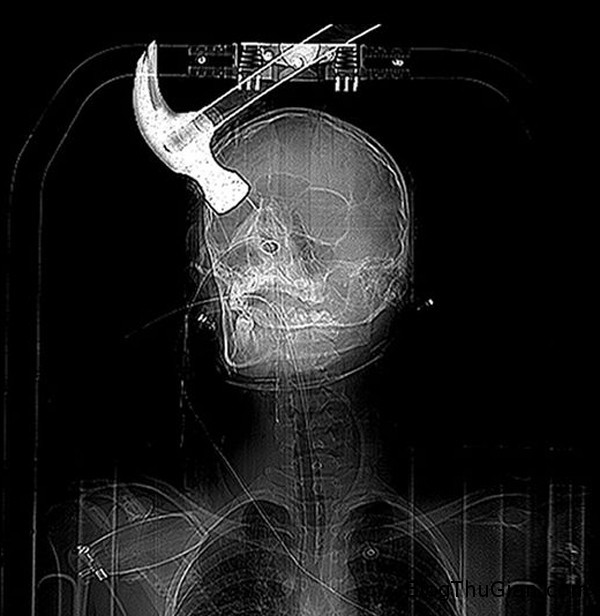

Hình chụp X-quang hộp sọ của Connor.

Ngày 28/5/2013, trong lúc đang nằm ngủ trên ghế tại căn hộ chung ở thị trấn Margate, hạt Kent, Anh Quốc, cậu thanh niên 18 tuổi Conner đã bị người bạn cùng nhà là Joseph Williams dùng búa đập vào đầu. Connor được đưa vào bệnh viện trong tình trạng chiếc búa vẫn găm chặt vào hộp sọ.

Connor Huntley bị méo một bên hộp sọ sau vụ tấn công dùng búa đập vào đầu.